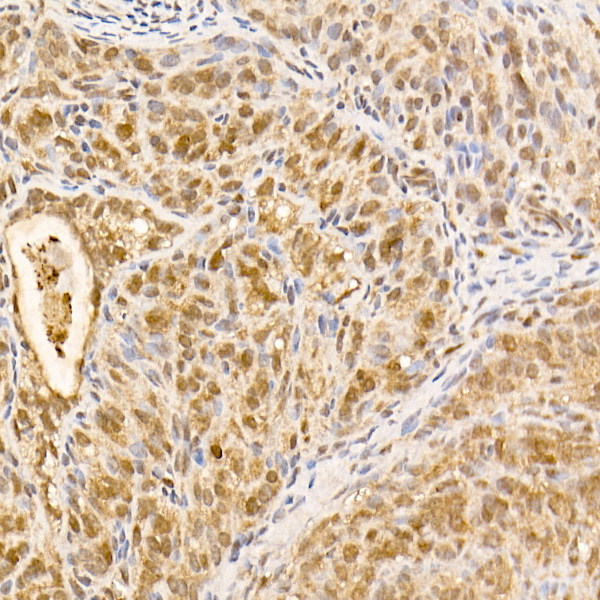

| Immunohistochemistry analysis of paraffin-embedded Rat ovary using [KO Validated] AKT1 Rabbit mAb (A22770) at dilution of 1:100 (40x lens). High pressure antigen retrieval performed with 0.01M Citrate Bufferr (pH 6.0) prior to IHC staining. |